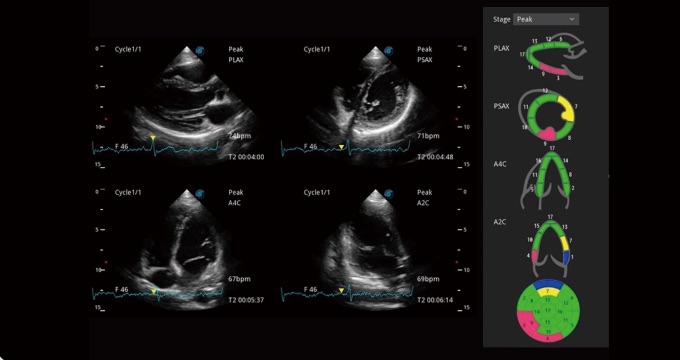

• 负荷超声心动图

支持运动和药物负荷协议、多心动周期存储选择,为临床观察心肌负荷状态下的室壁节段运动、评估心肌缺血状态提供更多的解决方案。